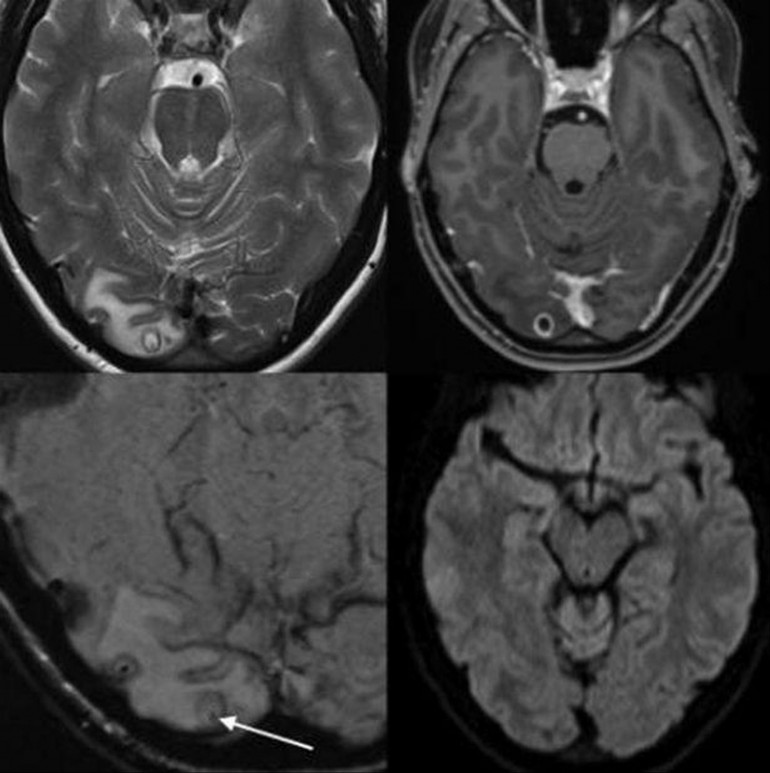

Une IRM a révélé la présence d'un tas de larve de ténia à l'arrière du cerveau de la jeune femme.

Depuis ses 18 ans, Rachel Palma, une serveuse de Melbourne, souffrait régulièrement de maux de tête ainsi que d'une baisse de vue inexpliquée. Lorsque la jeune femme se décide enfin à consulter un médecin, le corps médical lui diagnostique un kyste à l'arrière du cerveau. Une IRM a révélé qu'elle souffrait d'une lésion de 8mm de long dans le lobe occipital.

En réalité, la grosseur dont souffrait l'Australienne était un tas de larves de ténia, selon une étude de cas publiée dans The American Journal of Tropical Medicine and Hygiene et rapportée par le média The Independent.